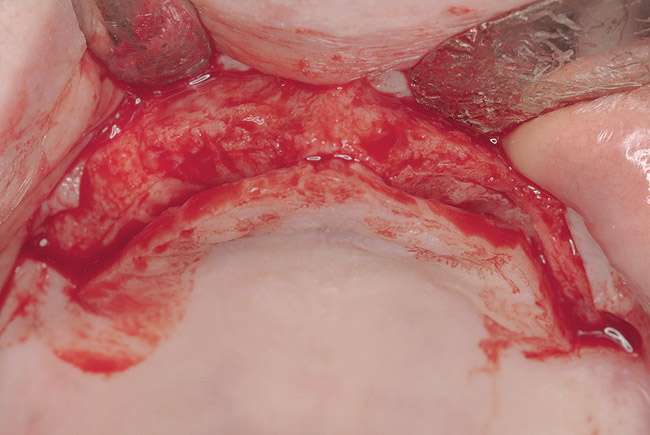

These patients were tested for two different treatment options; either a bar-supported overdenture requiring four implants in the first premolar area or anterior to the bicuspids, or a "simple fixed prosthesis" anchored by six implants placed bilaterally from first-molar-to-first-molar regions. When a flapless, guided surgery was contemplated, the investigators determined that based on the available maxillary bone, 70% of patients (28 implants) could undergo this treatment modality. Of the 40 patients, 15% could not have any implants placed due to inadequate bone height and width. For "simple fixed prostheses," only 30% (72 implants) of patients presented with adequate bone dimensions permitting a flapless guided placement of six maxillary implants placed symmetrically around their arch in a flapless manner. For the fixed treatment, 18% of patients could not have any implants placed due in insufficient bone dimensions. The authors concluded that advertisement of computer-guided, flapless solutions are "euphoric," and tend to overlook patients' individual oral and anatomic conditions. They felt that guided surgery does provide better control of implant placement leading to higher predictability of treatment outcomes. In a study where the accuracy of virtually placed implants and actual positions in a cadaver model were compared, Petterson et al7 found significant differences related to deviations in hex, apex, and depth of the two placements. Without the preparedness to temper treatment expectations or plan on delivery of the pre-fabricated "final" prosthesis immediately after surgery, these types of studies should lead clinicians to proceed with caution in these procedures. The efficacy of an open approach, one requiring a mucoperiosteal flap, may be improved upon with a guided approach in cases where severe ridge-resorption is treated, and may be more predictably handled using this technology. A bone-supported template, affixed to the alveolar ridge with fixation screws, can be fabricated with numerous software package and stereolithography (Figure 8 and Figure 9). A full-thickness flap is elevated, exposing the resorbed alveolar ridge (Figure 10). Using osseous fixation screws, the template is stabilized to the ridge, preventing any movement during osteotomy preparation (Figure 11). Using a sleeve-in-sleeve, manufacturer-specific surgical armamentarium, implants can be placed in the optimal positions, where the maximum amount of initial bone to implant contact is achieved. The anticipated bone augmentation procedures can then be performed, which is not possible with a closed procedure (Figure 12). The flaps are subsequently closed, allowing for the patient to wear any transitional, soft-relined denture. The surgical guide can also serve an important function at the time of implant uncovering. The location of the implants beneath the healed mucosa can be determined by seating the guide and sounding with a 30-gauge anesthetic needle. Using a tissue punch, the implants can be uncovered without flap elevation; the cover screws can be removed and the appropriately sized healing abutments can be placed (Figure 13). From this point forward, traditional prosthetic steps are followed to fabricate an implant-supported/retained overdenture.

Figure 10  Full-thickness flap of edentulous maxillary arch.

Figure 10